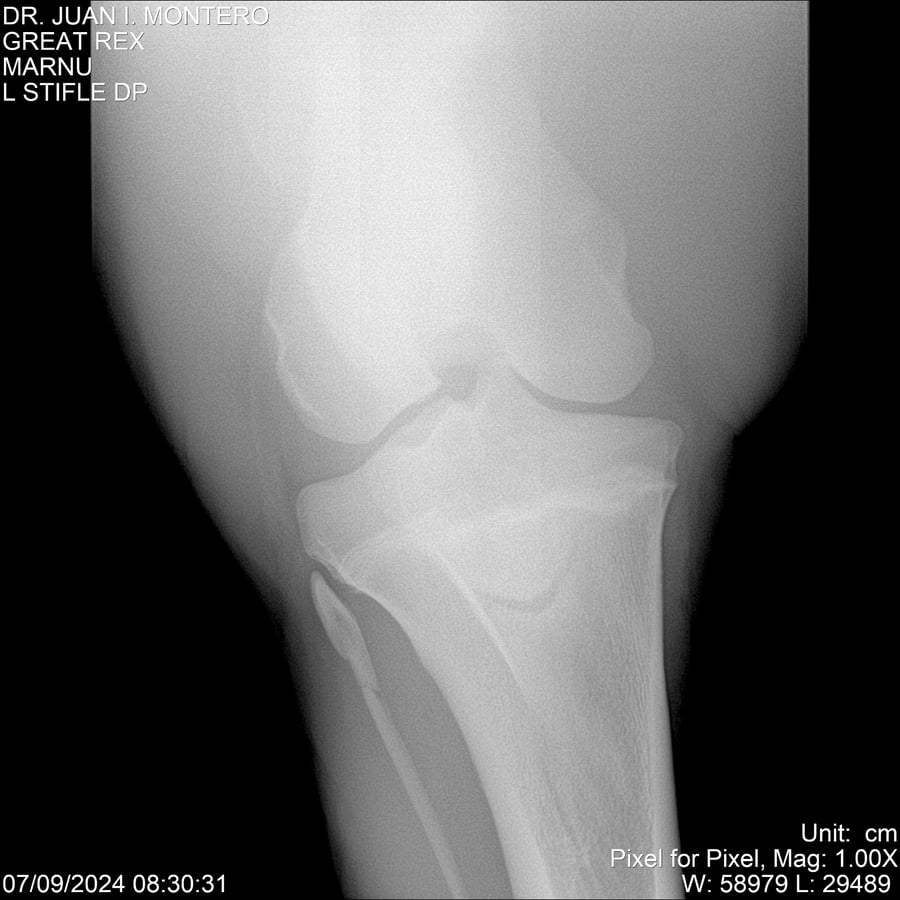

LOTE 4, GREAT REX Lote Anterior Volver al remate Lote Siguiente Ficha Contacto Montevideo - Ficha del Lote Identificador: #282518 Categoría: Yeguarizos Montevideo - 66 Visualizaciones ClicData Contacto Empresa: Abelenda N. R., Walter Hugo Nombre*: Teléfono* : E-mail* : Mensaje Enviar Registrese gratis Este contenido Exclusivo está disponible sólo para usuarios registrados Ingresar